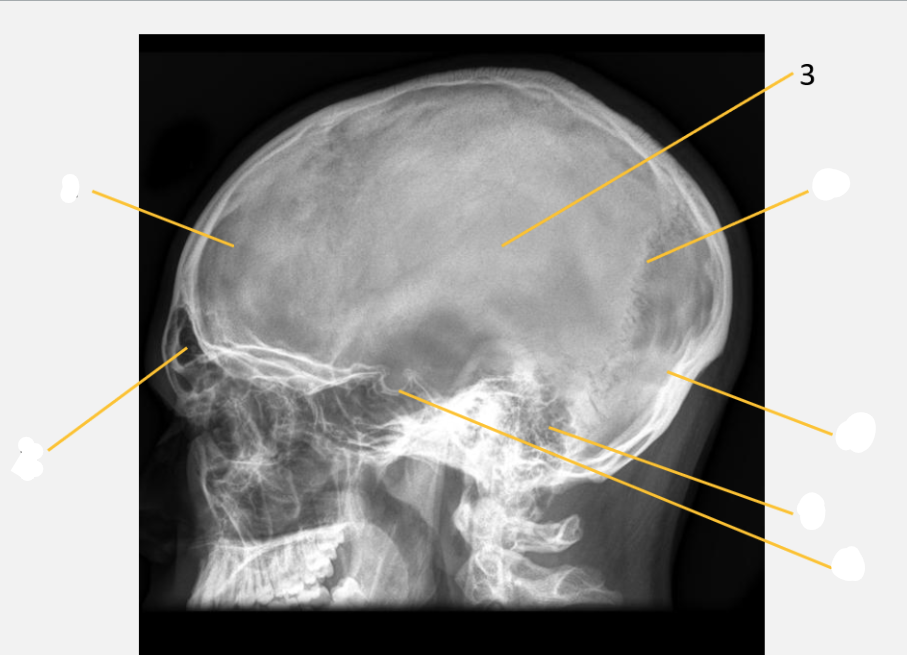

frontal bone

frontal sinus

parietal bone

lambdoid suture

occipital bone

mastoid air cells

Sella turcica

inferior orbital rim

maxillary sinus

zygomatic arch

petrous ridge

angle of mandible